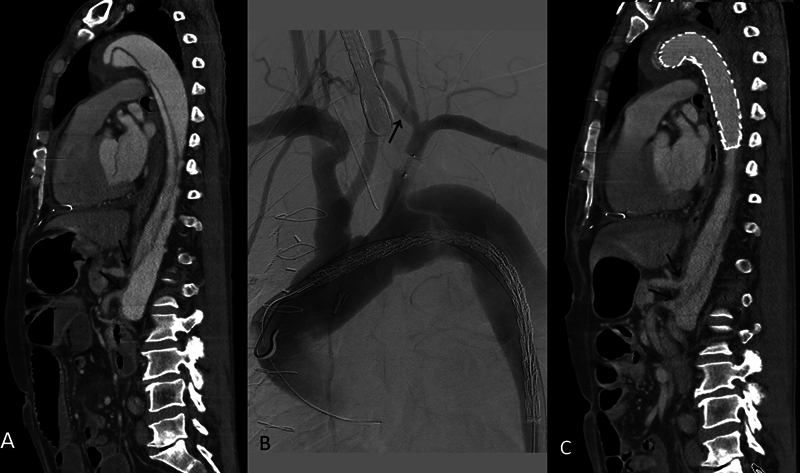

The distal extent of aortic repair in acute aortic dissection and the management of malperfusion in terms of timing and strategy are still debated topics. We present a case of acute type B dissection with retrograde extension to the ascending aorta, with the most proximal intimal tear in the descending thoracic aorta, associated with both early lower extremity and delayed mesenteric malperfusion syndrome, treated effectively by femoral artery open fenestration and hybrid zone 2 arch repair.